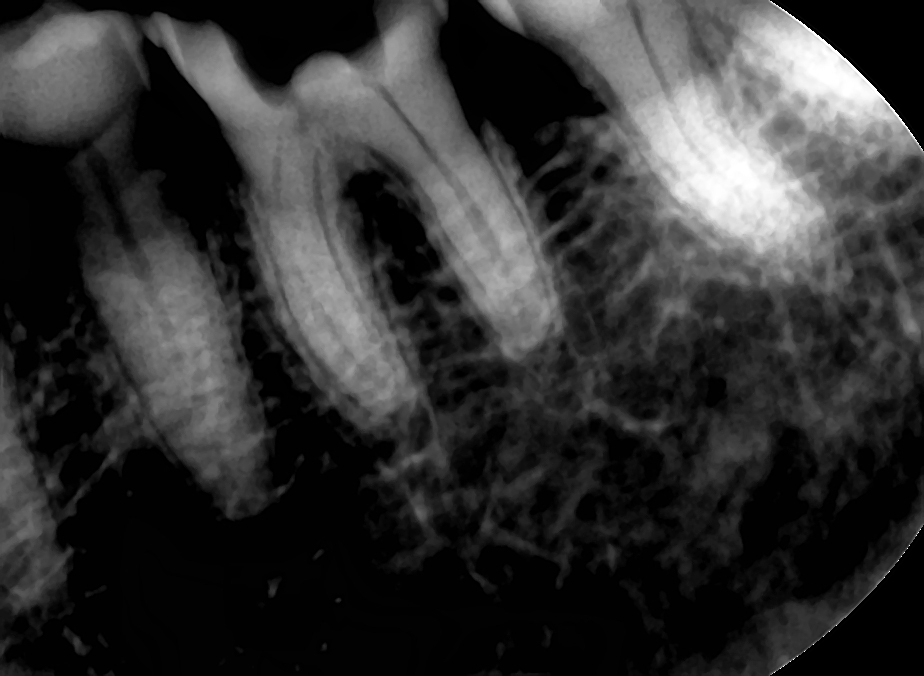

말이 나와서 그런데 이번 주 어려웠던 엔도 케이스는 바로 이 케이스였다. 치수강이 뭐 거의 없다시피 했고 그래서 오리파이스 입구는 완전히 ㄱ자로 꺾여있는.. 그래서 밑으로 밑으로 한겹씩 벗겨내다가 쫄려서 사진 한 장 더 찍은 게 아래 왼쪽 periapical 사진이다. 엑스레이 상에서 근관 보이길래 그래도 수월할 줄 알았는데 전혀 아니었다. buccal 부터 distobuccal 교두가 치은 마진 레벨까지 완전히 파절돼서 오셨고 그래서 AO 쉬울 줄 알았는데..ㅠㅠ

C-Pilot file 6-8-10 > V-Taper2H NiTi file 20 > ProTaper Universal S1 brushing > VT2H 25-30 > GG-bur 4 순서로 사용

저렇게 사진 찍어보고도 한참을 더 외하방으로, 그리고 또 옆으로(troughing), 살살 살살, 물을 껐다가 물 다시 켰다가.. 겨우겨우 오른쪽 사진처럼 만들어놨다. 만 89세 어머니. C파일도 구부러져서 몇개를 버리고, PTU S1도 부러질까봐 새거 까서 쓰면서도 불안해 해야하고, VT2H도 풀려서 버리고(10번 후에 바로 20번 써서 그런 것도 있지만). 그리고 저만큼 해놓은 저것도 furcation부위 바닥 더 까서 확실히 바닥이 맞는지 확인해봐야한다. 아무튼 이런 케이스 하다보니 엄지손가락 끄트머리에 마치 기타 처음 칠때처럼 각질이 벗겨지고 감각이 hypersensitive해져버렸다. 굳은살이 생기려나 보다.